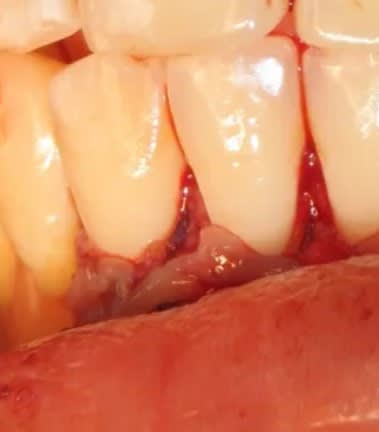

mais serieusement, la c'était vraiment fini ? elle est allée en salle de réveil comme ca ?? :

non, comme ça!

donc elle est bien allee en salle de reveil non suturee... vache...

la sincèrement c est quand meme pas terrible... je veux bien rigoler un peu mais ca c est pas acceptable.

a moins que pas suturer ce soit aussi pour simplifier...